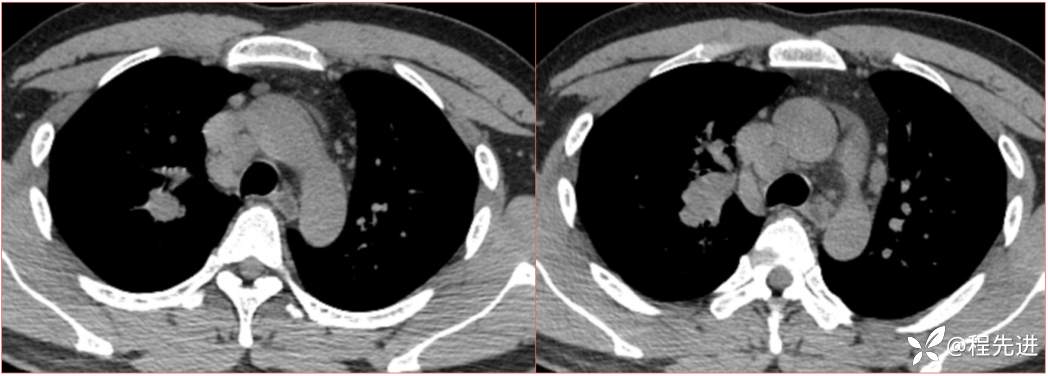

简要病史:患者一周前无明显诱因出现阵发性刺激性咳嗽,咳少量白色粘液痰,咳嗽无明显昼夜节律性,无发热、畏冷、寒战,无头痛、胸闷、胸痛,自行服药后 (具体不详) 症状无缓解,3天前外院胸片检查示右上病变

辅助检查:肺肿瘤标志物:神经元特异性烯醇化酶(NSE):35.72ng/ml(参考值0-16.3);非小细胞肺癌相关抗原211、胚抗原糖类抗原125、铁蛋白、鳞状细胞癌抗原未见异常